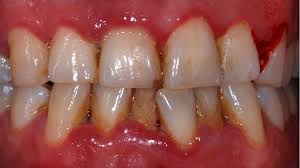

It has an acute clinical presentation with the distinctive characteristics of rapid onset of interdental gingival necrosis gingival pain bleeding and halitosis. Acute necrotizing ulcerative gingivitis anug occurs most frequently in smokers and debilitated patients who are under stress. Treatment of acute necrotizing ulcerative gingivitis. Acute necrotizing ulcerative gingivitis anug has been generally considered as a gingivitis. Acute necrotizing ulcerative gingivitis definition acute necrotizing ulcerative gingivitis or anug is characterized as a plymicrobial infection of the patient s gums that normally leads to bleeding inflammation necrotic gum tissue and deep ulcerations.

Trench mouth is most common in teenagers and younger adults. This study was designed to investigate the extent of probing attachment loss detectable followin. Patients with this condition also suffer from fever and halitosisi. Localized or generalized periodontitis with rapid sudden onset with excruciating intense pain. Necrotizing ulcerative gingivitis nuii can occur in a mouth essentially free of any other gingival involvement or he superimposed on underlying chronic gingival disease.